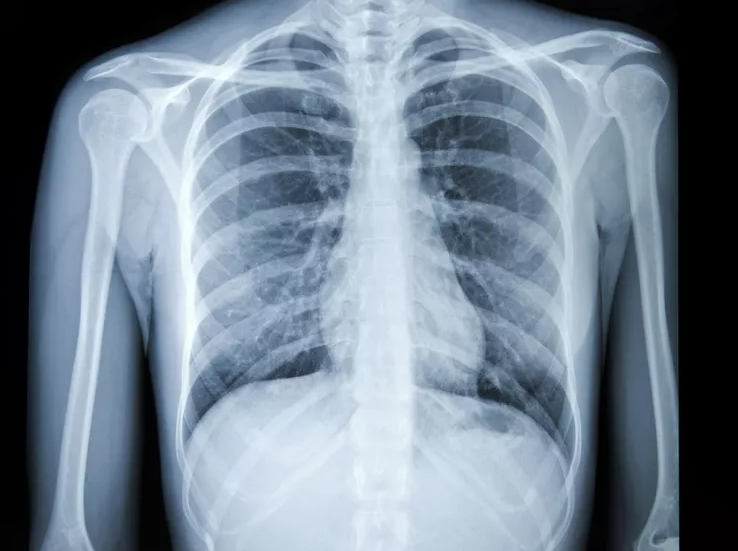

Chest X-Ray Lung Disease Detection

Advanced AI system for detecting and analyzing lung diseases from chest X-ray images.

- Medical image analysis and interpretation

- Early disease detection capabilities